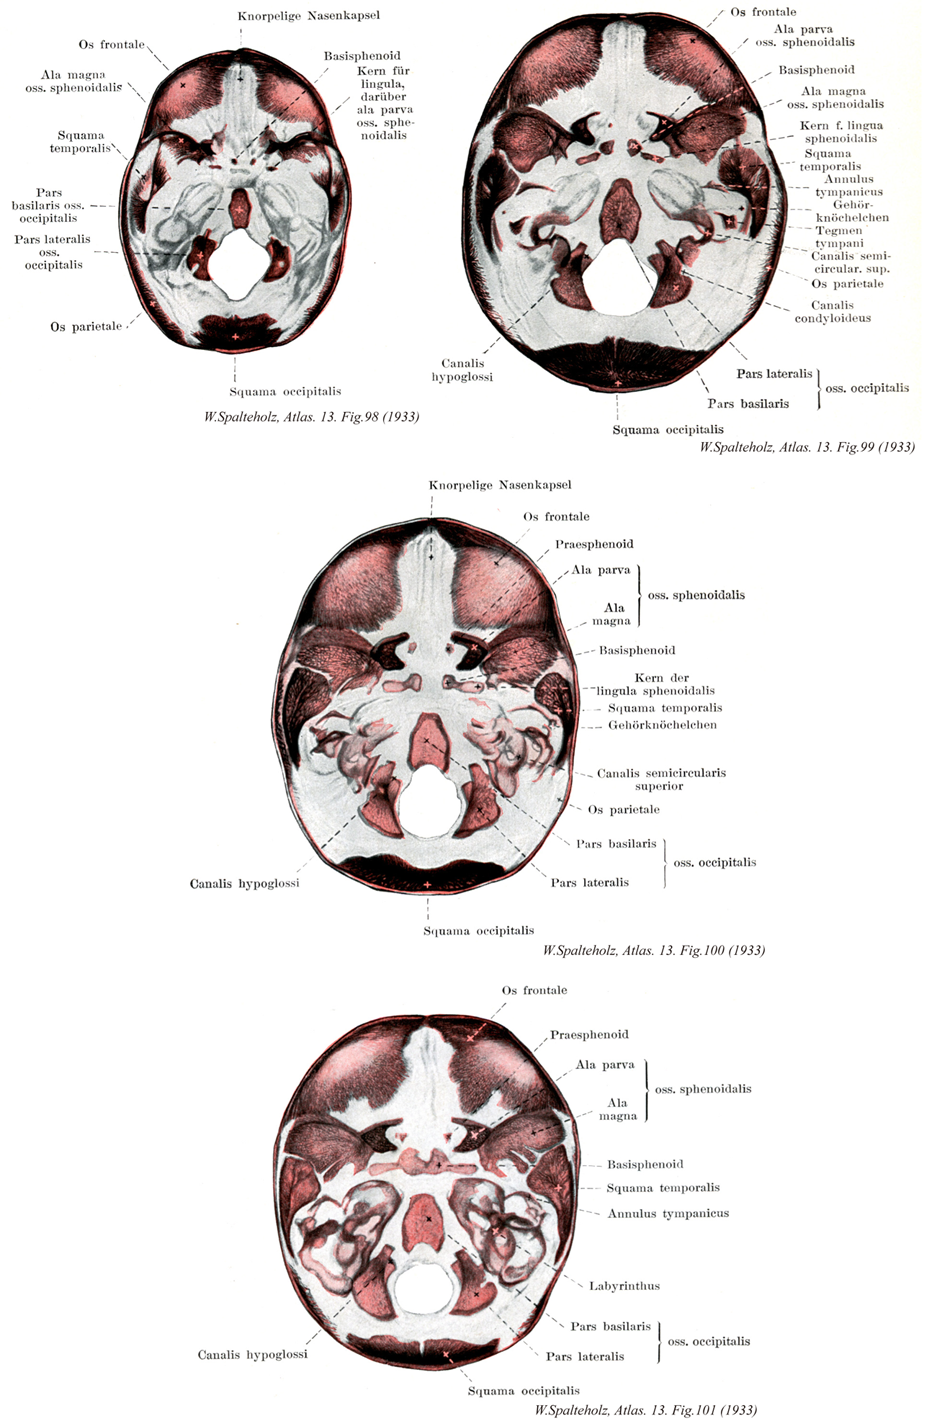

098

- 098_01【Frontal bone前頭骨 Os frontale】

- 098_02【Greater wing of sphenoid bone大翼(蝶形骨の) Ala major; Ala magna (Ossis sphenoidalis)】

- 098_03【Temporal squamous of temporal bone側頭鱗(側頭骨の) Squama temporalis】

- 098_04【Basilar part of occipital bone底部(後頭骨の) Pars basilaris (Os occipitale)】 The part that ascends from the foramen magnum to the spheno-occipital synchondrosis.

- 098_06【Parietal bone頭頂骨 Os parietale】 Bone located between the occipital, frontal, sphenoidal, and temporal bones.

- 098_07【Basisphenoid頭底蝶形骨 Basisphenoid】

- 098_08【Sphenoidal lingula蝶形骨小舌;蝶形小舌;蝶形骨小唇 Lingula sphenoidalis】 Pointed process that is located lateral to the entrance of the internal carotid artery into the cranial cavity.

- 098_09Ingrassia's process【Lesser wing of sphenoid bone小翼(蝶形骨の) Ala minor; Ala parva (Ossis sphenoidalis)】

- 098_10【Squamous part of occipital bone後頭鱗(後頭骨の) Squama occipitalis】 The part that is posterior to the foramen magnum.